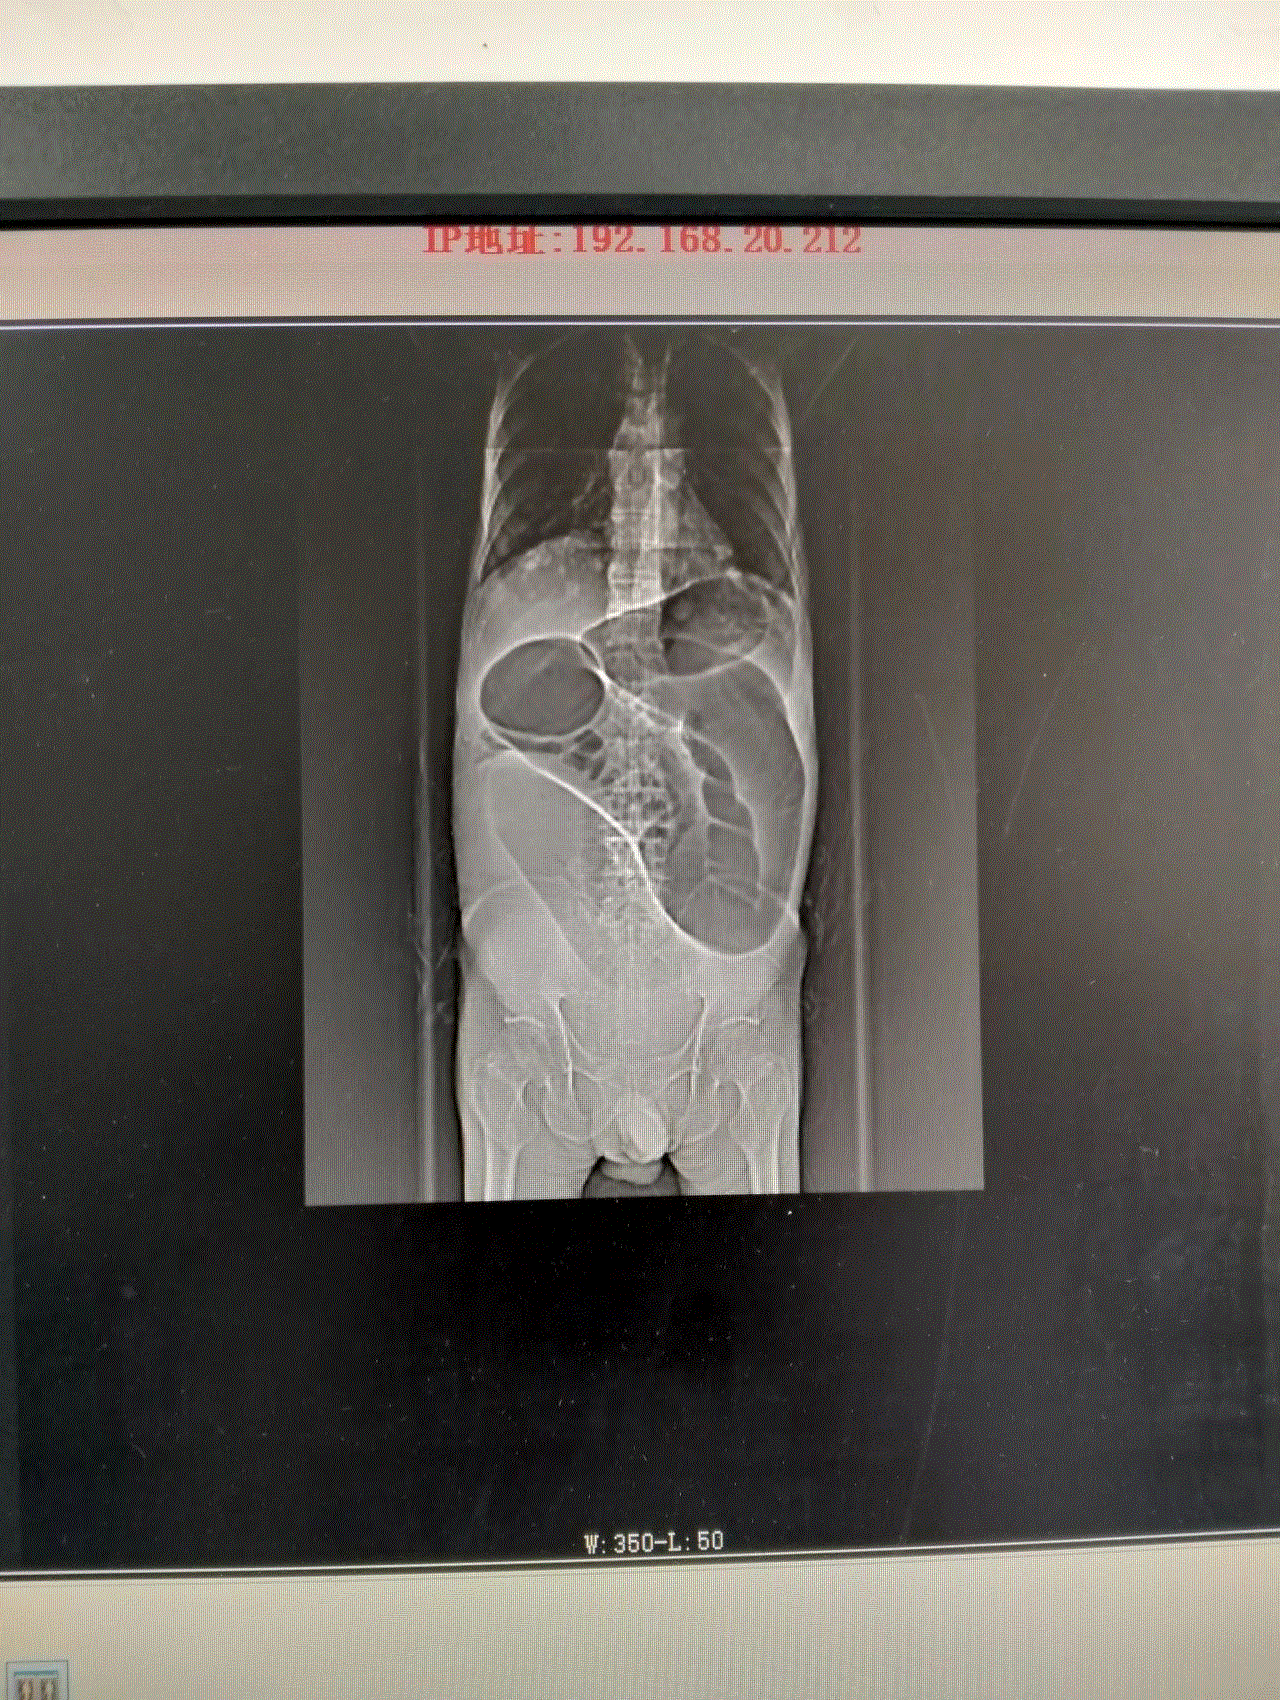

此时的龚大爷,腹部高高隆起,犹如临产的孕妇,叩诊鼓音明显,情况危急!CT显示,龚大爷的结肠严重扩张,脏器被挤压移位。若不及时解除梗阻,随时可能引发腹膜炎、感染性休克,甚至危及生命。然而,常规胃肠减压对低位肠梗阻效果有限,治疗陷入僵局。